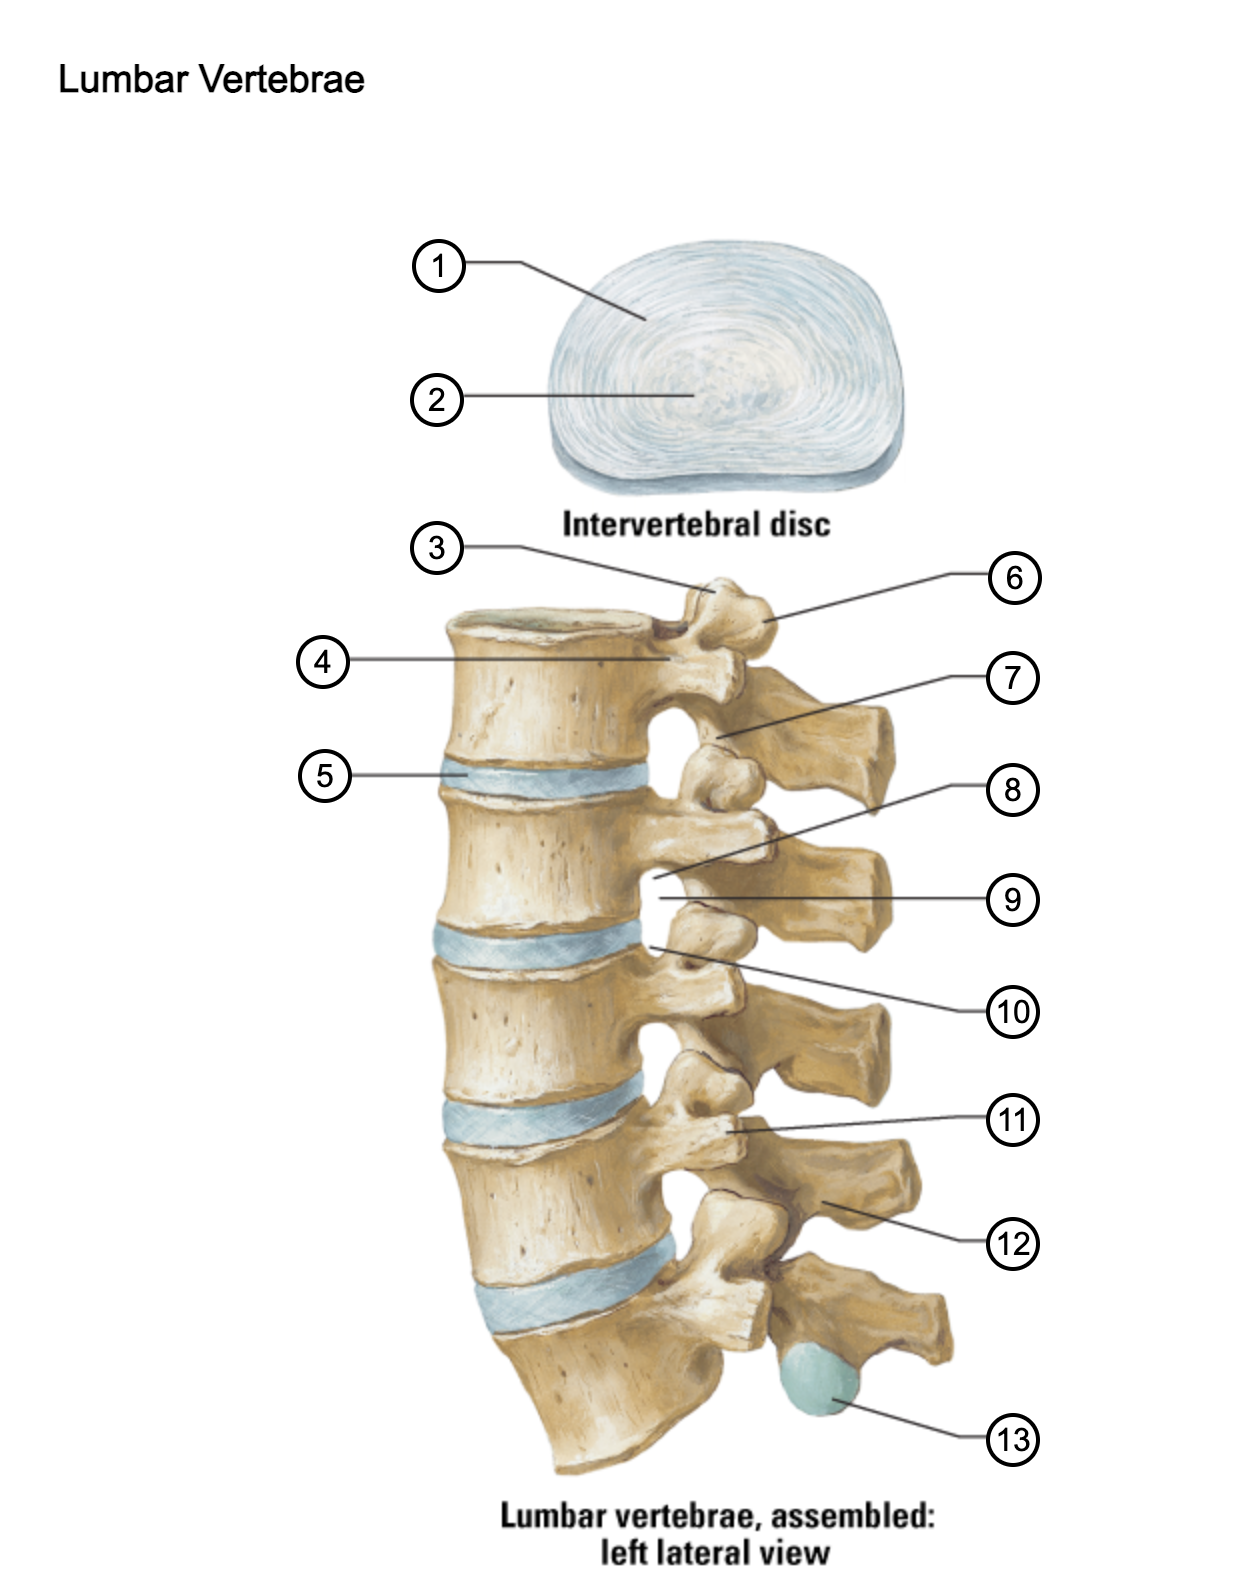

1

anulus fibrosus

2

nucleus pulposus

3

superior articular process

4

pedicle

5

intervertebral disc

6

mammillary process

7

inferior articular process

8

inferior vertebral notch

9

intervertebral notch

10

superior vertebral notch

11

transverse process

12

lamina

13

inferior articular facet